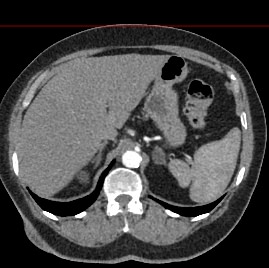

Современным высокоинформативным способом выявления патологических изменений поджелудочной железы является мультиспиральная компьютерная томография с прицельным сканированием органа. Метод КТ основан на применении рентгеновского излучения и способности органов и тканей поглощать рентгеновские лучи.

При необходимости детальной визуализации структуры железы, особенно в случае подозрения на развитие опухоли, назначается КТ поджелудочной железы с контрастом. Для этого применяются йодсодержащие контрастные препараты, которые вводятся пациенту внутривенно. Контрастное вещество, попадая в кровоток, контрастирует кровеносные сосуды и патологические очаги на фоне окружающих здоровых тканей.

Контрастирование позволяет отличить зоны воспаления, деструкции, разрастания фиброзной ткани и опухолевой трансформации от сохраненной паренхимы поджелудочной железы. КТ поджелудочной железы с контрастированием дает исчерпывающую информацию о состоянии органа и патологических процессах в нем.

При помощи специальных цифровых приложений данные, полученные при сканировании, преобразуются в трехмерные изображения органа, что дополнительно повышает точность и достоверность диагностики заболеваний поджелудочной железы.